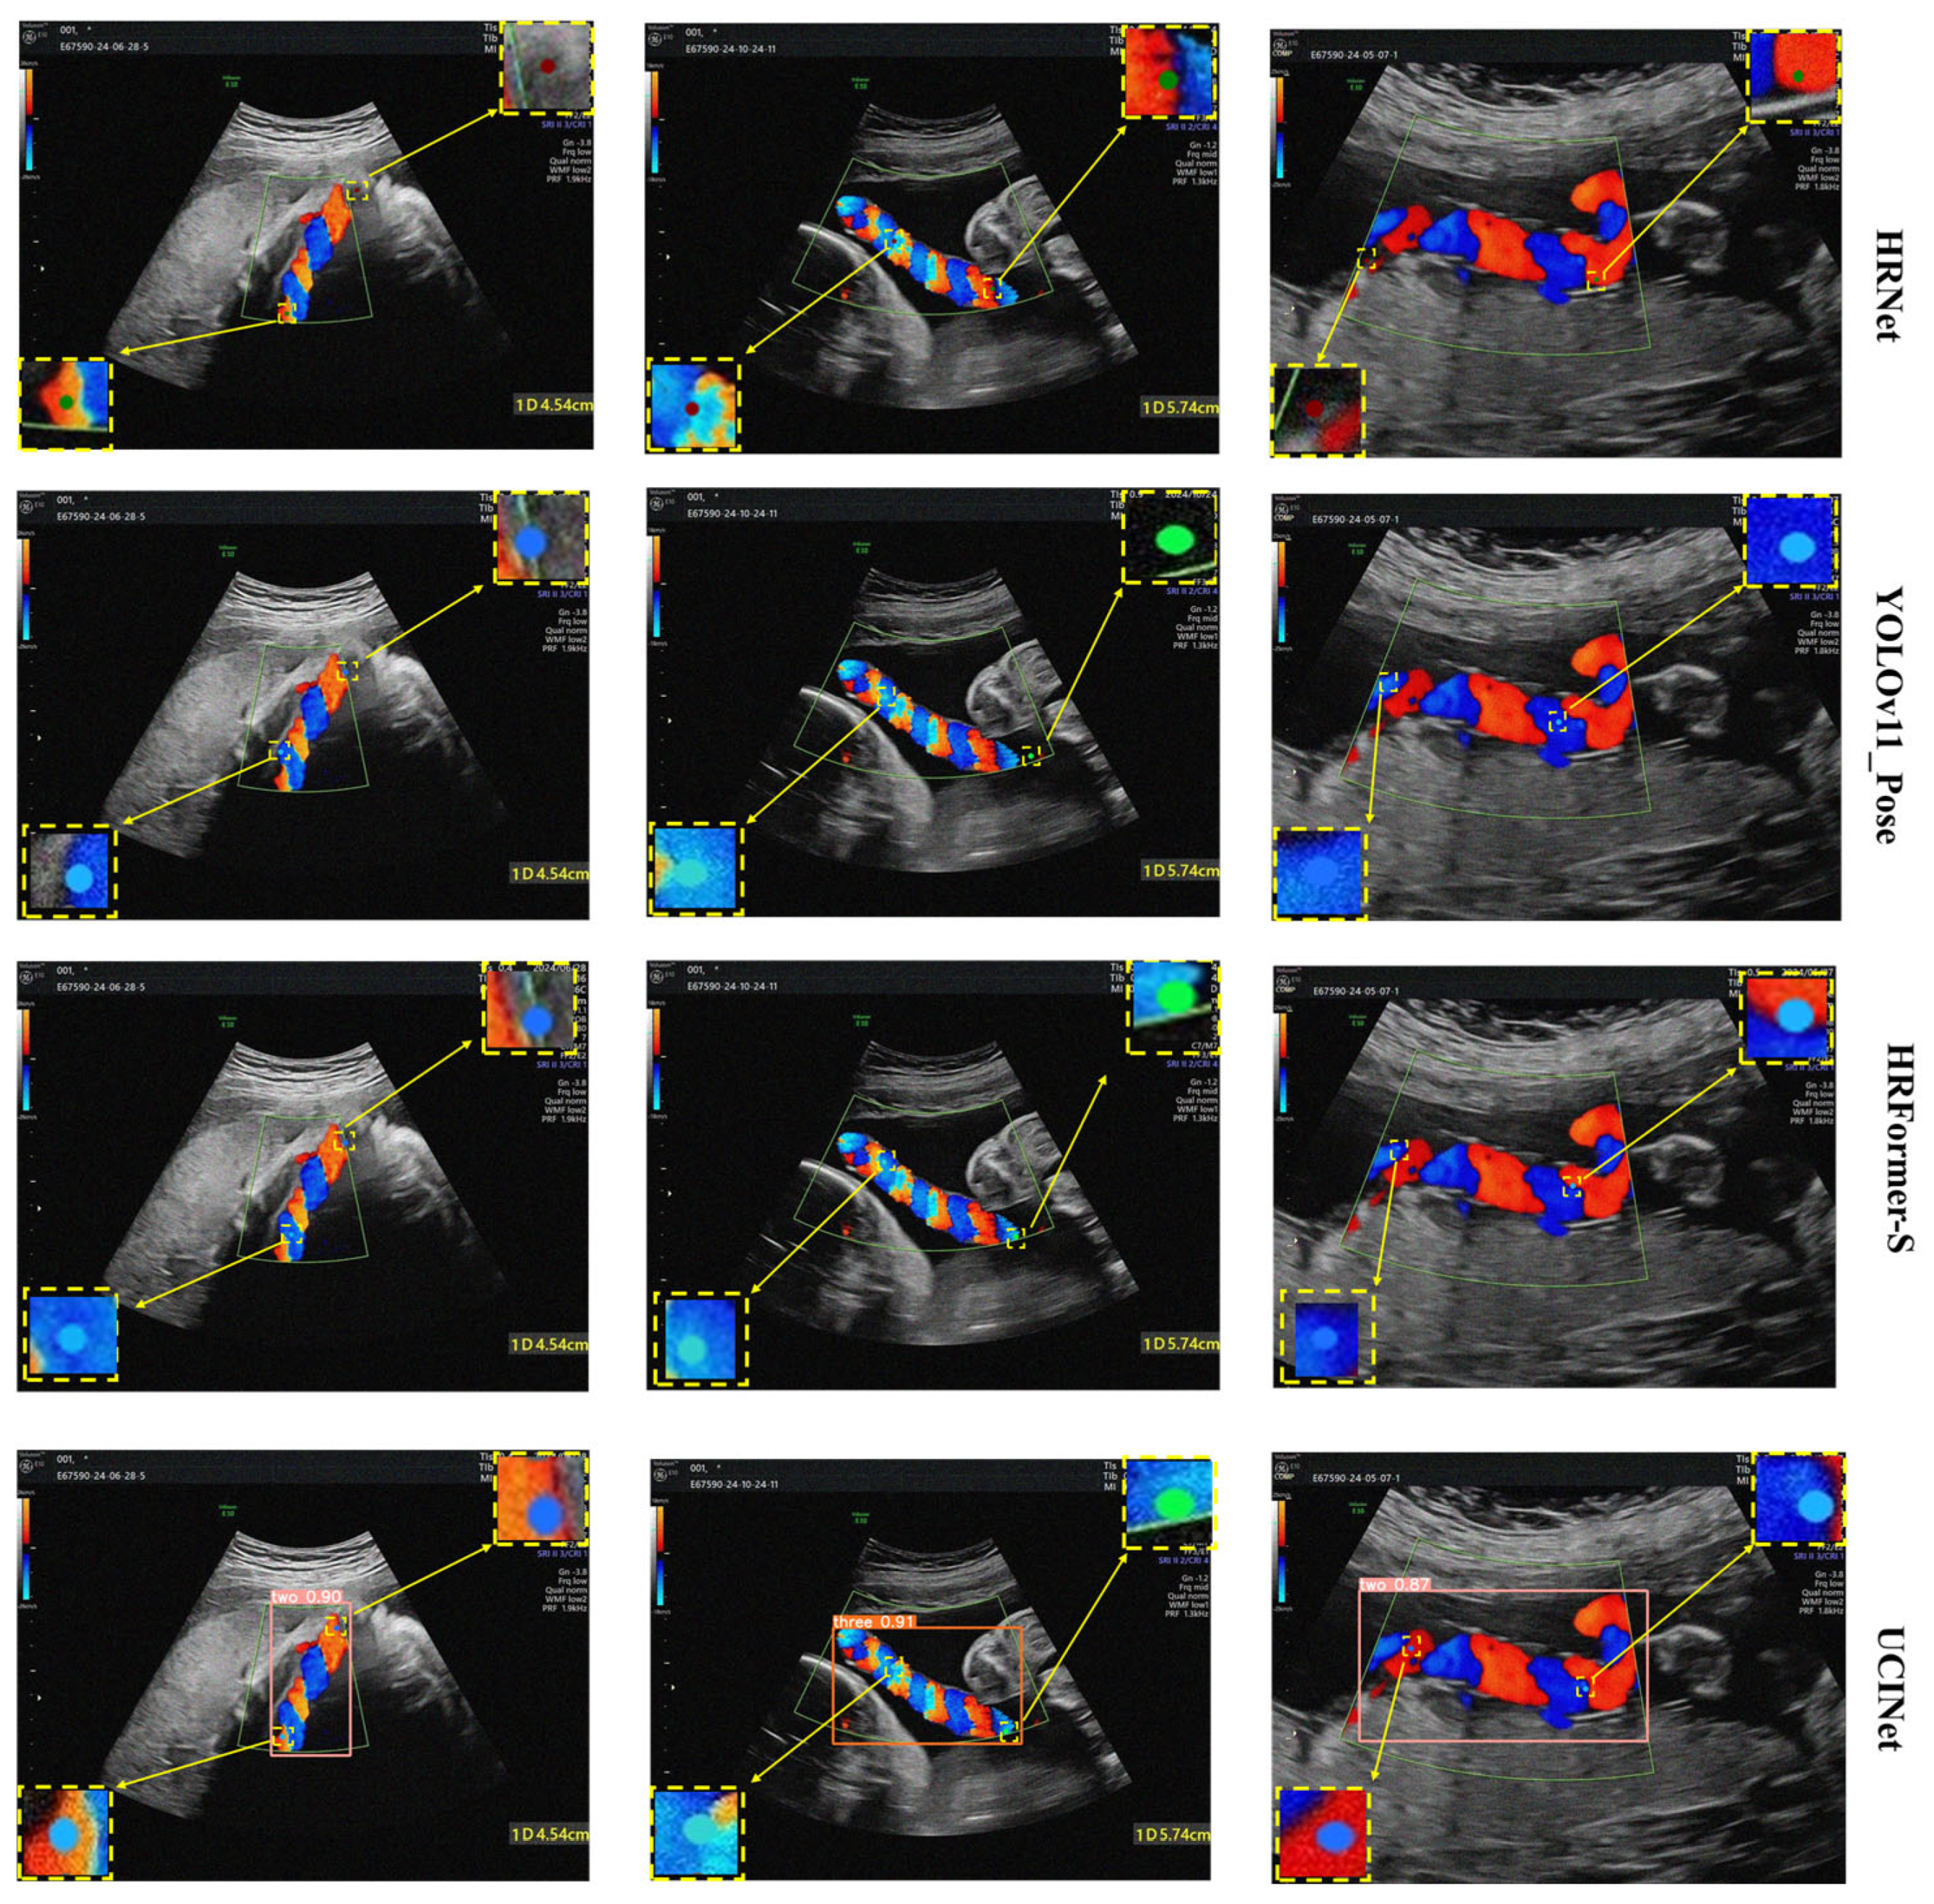

For keypoint detection task, UCINetwas compared with several representative models, including the widely adopted HRNet [37], the transformer-based HRFormer-S [38], and lightweight approaches, such as YOLOv5_Pose and YOLOv11_Pose. We comprehensively evaluated the UCI and Ear210 datasets to analyze the model’s performance across diverse domains.

On the UCI dataset, UCINet achieved the highest overall accuracy and efficiency. As summarized in Table 3, UCINet attains a mAP@50 of 88.4% and a mAP@50–95 of 75.4%, outperforming HRNet (+2.5% mAP@50, +0.8% mAP@50–95) and HRFormer-S (+1.3% mAP@50, +0.5% mAP@50–95), despite requiring only one-third of their parameters (9.2 M vs. 28.5–32.1 M). Furthermore, UCINet delivers 109 FPS, 5–6 times faster than HRNet and HRFormer-S, indicating superior real-time capability. Compared with lightweight baselines, UCINet provides notable accuracy gains of 4.9% and 5.3% in mAP@50 and mAP@50–95 over YOLOv5_Pose, and 1.6% and 2.6% over YOLOv11_Pose, while maintaining a comparable parameter budget, highlighting its enhanced localization precision and robustness. The visualization results in Figure 9 further illustrate that UCINet identifies umbilical cord endpoints with sharper localization and higher confidence, whereas YOLO-based baselines occasionally suffer from drift or partial misalignment.

On the Ear210 dataset, UCINet also demonstrates strong generalization ability. As shown in Table 4, UCINet achieves a mAP@50 of 86.2% and a mAP@50–95 of 50.5%, surpassing HRNetby 7.7% and 7.3%, HRFormer-S by 5.0% and 4.0%, and YOLOv5_Pose by 6.1% and 4.8%, respectively. Compared with the stronger YOLOv11_Pose baseline, UCINet achieves improvements of 3.0% in mAP@50 and 2.3% in mAP@50–95. Figure 10 illustrates that UCINet produces more reliable endpoint localization under challenging conditions, such as blurred edges or complex ear anatomy, where competing models show apparent deviations. In summary, UCINet effectively balances accuracy, efficiency, and model compactness in keypoint detection. It consistently outperforms CNN-, Transformer-, and YOLO-based baselines across private and public datasets, confirming its superior robustness and strong potential for deployment in clinical applications.

Figure 9. Visualization of keypoint detection results of UCINet and other methods on the UCI dataset.

Figure 10. Visualization of keypoint detection results of UCINet and other methods on the Ear210 dataset.